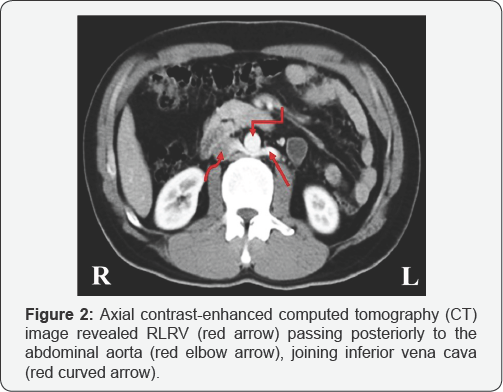

A 38-year-old male was referred to the radiology clinic because he had periodic left flank pain without a history of trauma, kidney stone, kidney and urinary tract infections and other diseases. He suffered from these conditions for several months. There were no fever and trembling. Vital signs, including blood pressure, blood oxygen level, respiratory and heart rate were normal. Blood and urine tests showed normal levels of inflammatory factors, creatine, as well as urea. The ultrasonography and CT scan (as contrast-enhance) of abdomen and pelvis were performed for diagnosis. Obtained images revealed that the left renal vein located between the abdominal aorta and lumbar vertebral body (Figures 1 & 2). The other abdominal-pelvic organs had the normal position. The patient was informed about the process of medical imaging and the consent was obtained from him.

RLRV is classified in 1995 by Hoeltl et al. [8] into two types, I and II. In type I, RLRV has orthotropic status, while, in type II, the left renal vein moves downward combined with the lumbar and gonadal (testicular or ovarian) veins before passes through behind the aortic artery and drains into the inferior vena cava [8]. Our case seems to be classified as type I. In another classification, which was present in 2007, the RLRV has been divided into four groups based on the type of blood drainage [9] (Figure 3). Type I: drainage of RLRV to the inferior vena cava occurs in the orthotropic status; Type II: the RLRV drain to the ICV at the level of the L4-L5; Type III: the LRV, which consists of anterior and posterior branches, therefore, the vein is called collar LRV; Type IV: the RLRV drains into the left common iliac vein [9]. Our suggestion is that the present case is classified as type I. Imaging techniques such as CT scan, MRI, and ultrasonography are useful methods to diagnose the RLRV. Unaware of the existence of RLRV can cause irreparable events such as bleeding and even death during the retroperitoneal surgery of the abdomen [10]. Surgeons prefer the left renal vein in renal transplantation because of its longer length. Hence, it is important to know the course of the left renal vein whether it is preaortic or not. It is also important to be aware of anomalies of the renal vein for distinctive diagnosis of retroperitoneal tumors, retroperitoneal lymph node pathologies, and aortic dissection [11]. However, during any operations, lack of knowledge about anatomical variations, for example, variations in the peripheral nerves, organs, etc., may make a hard situation for surgeons and leads to a possible mistake during surgery [12-14].